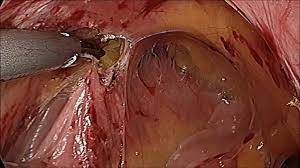

Ovarian Cystectomy by Laparoscopy for Dermoid Cyst

Laparoscopic Surgery for Endometrial Cyst

Left Sided Ovarian Cyst Laparoscopic Approach

Laparoscopic Myomectomy for Intramural Myoma

Laparoscopic Hysterectomy Surgery for Large Uterus